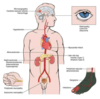

DM T2 Complications